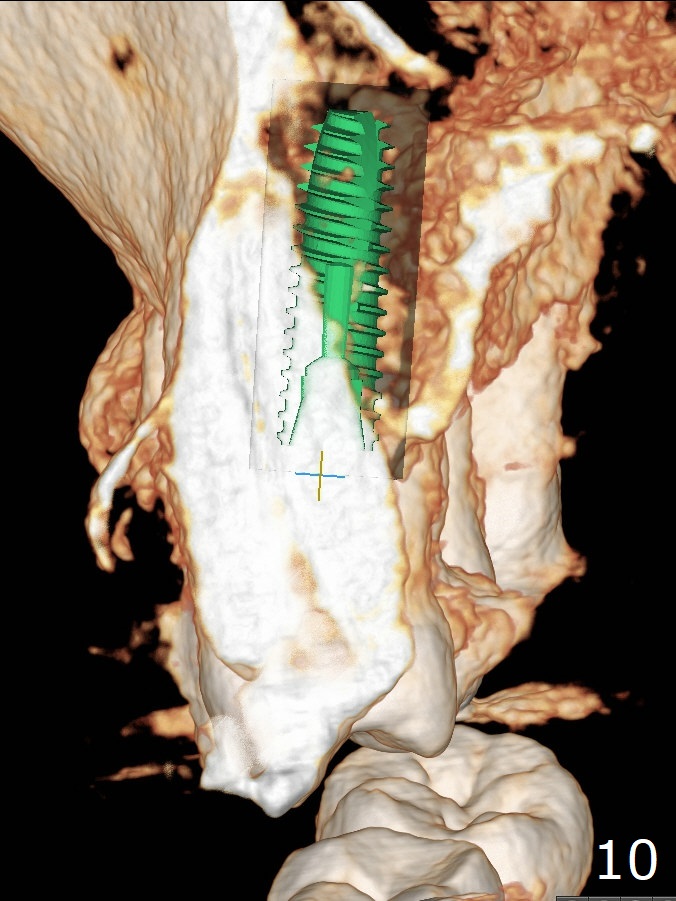

A 62-year-old man had traumatic root fracture at #6 in his teen. The tooth remained asymptomatic until his fifties. Following root canal therapy (Fig.1), the tooth is orthodontically extruded (~ 5 years, Fig.2 (*: bracket)) with apparent disappearance of the infection. The bone distal to #7 seems to increase in height (Fig.3, as compared to Fig.1) and in density (Fig.4). Bone graft could be placed for regeneration with PRF or GEM21S (Fig.5 red (between #6 and 7), pink (buccal to #7 or coronal to the fracture line) circles). With extrusion, the oblique fracture line is more than half or two third supragingival (Fig.6). In spite of severe bone loss, exostosis is present (Fig.7 (mesiobuccal view) E) so that bone graft could be placed palatal to it (Fig.8 red). In case the tooth is non-salvageable, immediate implant will be placed with guide (Fig.9,10). Move lingual button as apical as possible (Fig.12) and make occlusal clearance. Continue extrusion until all of the crack is exposed without deep pocket.